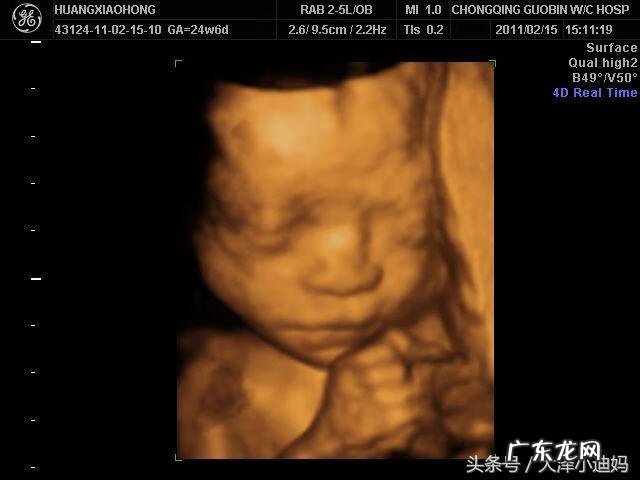

四维彩色超声诊断仪是目前世界上最先进的彩色超声设备 。它能够显示未出生的宝宝的实时动态活动图像,或者其它人体内脏器官的实时活动图像 。所以很多孕妈妈为了可以看一下宝宝的模样,都会照四维彩超 。

四维彩超与普通b超有一定的区别,第一,通过四维彩超可实时观察人体内部器官的动态运动 。第二,多方位、多角度地观察宫内胎儿的生长发育情况,为早期诊断胎儿先天性体表畸形和先天性心脏疾病提供准确的科学依据 。第三,B超设备只能检查胎儿的生理指标,而四维彩超还能对胎儿的体表进行检查,如唇裂,脊柱裂等发育不良,做到了及时发现,及时治疗 。所以四维彩超是有必要做 。

做四维彩超有一定的最佳时间,做四维彩超的最佳时间为怀孕5-7(20-28周)个月,因为这个时段胎儿的肢体及各主要脏器已经全部发育,而且羊水较适合做胎儿畸形筛查 。但因为孕妇的个体差异,个人的具体时间还请根据医生定的时间 。